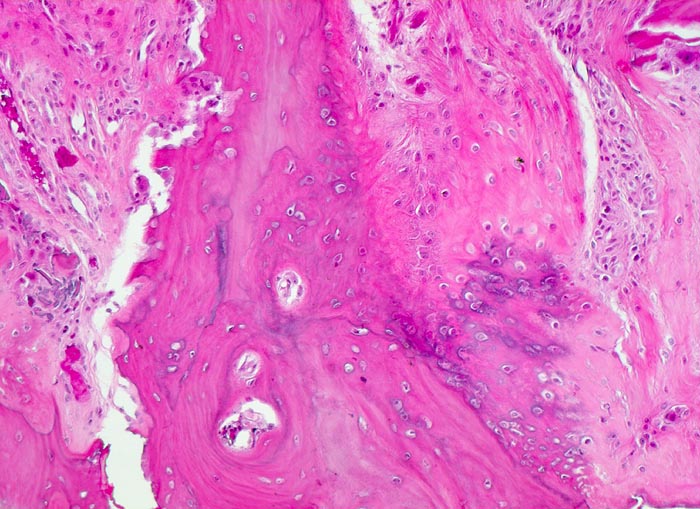

PathoPic – image database / PathoPic ID 4784 - aseptische Femurkopfnekrose

aseptische Femurkopfnekrose

vaskulär / Durchblutungsstörung

Knochen, Femurkopf

Gesteigerte Umbauphänomene in der Nekrosezone: Ortsständiger Lamellenknochen wird als Leitschiene zur Fasernknochenneubildung benutzt. Auf der gegenüberliegenden Seite wird der Lamellenknochen von Osteoklasten resorbiert. Kleine avitale Knochensequester. Granulationsgewebe.

Histologie

100